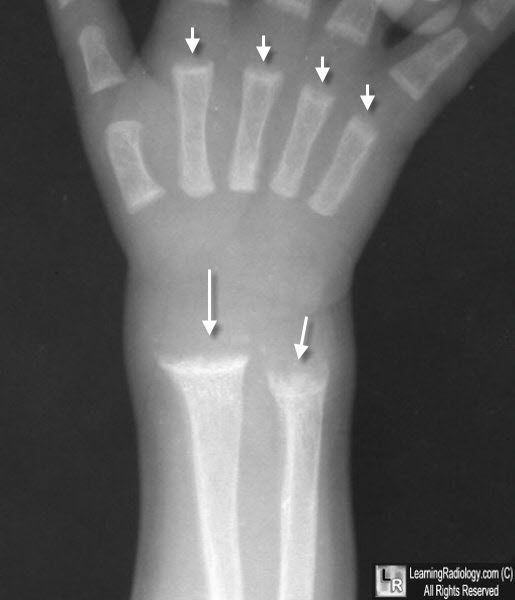

Rickets is a disease characterized by inadequate mineralization of bones in children which may be secondary to nutritional deficiencies or some other disorder. It causes softening of bones. Radiological findings in case of Rickets are: - fraying of metaphysis - cupping of concavity on metaphysis - splaying of metaphyseal ends Reference: https://radiopaedia.org/articles/rickets Image via: http://learningradiology.com/archives04/COW%20088-Rickets/ricketscorrect.htm